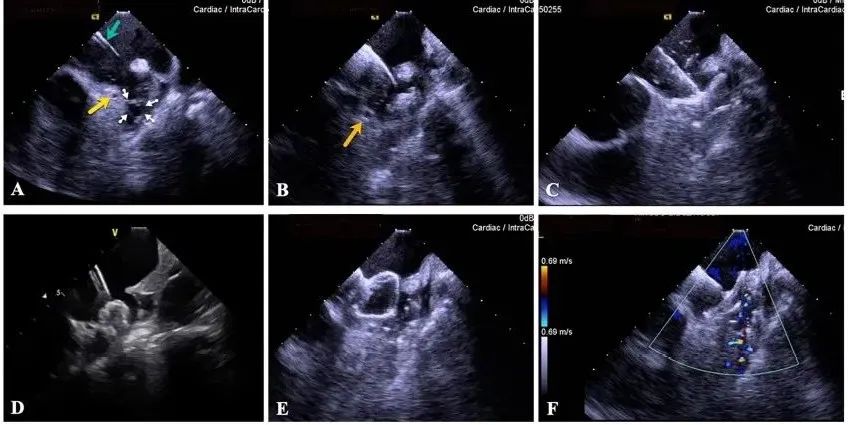

一種與心導(dǎo)管檢查相結(jié)合的超聲心動(dòng)圖診斷新興技術(shù),通過將超聲探頭置于心腔內(nèi)部,發(fā)射并接收超聲信號(hào),來(lái)精確獲取心臟解剖結(jié)構(gòu)、心臟血流動(dòng)力學(xué)等信息的實(shí)時(shí)成像。與其他影像技術(shù)相比,ICE技術(shù)具有操作簡(jiǎn)單、無(wú)輻射、安全性高、手術(shù)效率高、實(shí)用等優(yōu)勢(shì),ICE在很大程度上有望取代經(jīng)食道超聲心動(dòng)圖(TEE),成為電生理和結(jié)構(gòu)性心臟病領(lǐng)域的理想成像方式。

目前ICE技術(shù)已被應(yīng)用于左心耳封堵、房顫射頻消融、二尖瓣成形、房間隔缺損封堵等多種心臟介入手術(shù),應(yīng)用場(chǎng)景主要圍繞臟電生理、結(jié)構(gòu)性心臟病等領(lǐng)域,目前以電生理應(yīng)用為主。數(shù)據(jù)顯示,我國(guó)結(jié)構(gòu)性心臟病介入器械市場(chǎng)規(guī)模已從2017年的4億元增長(zhǎng)至2021年的20億元,年復(fù)合增長(zhǎng)率達(dá)48.3%;預(yù)計(jì)到2025年,該市場(chǎng)規(guī)模將達(dá)到104億元,可以預(yù)見ICE市場(chǎng)規(guī)模也將同步高速增長(zhǎng),未來(lái)市場(chǎng)發(fā)展空間廣闊。

心腔內(nèi)超聲(ICE)技術(shù)壁壘極高,國(guó)內(nèi)主要廠商核心部件仍舊為進(jìn)口,集成了超聲和圖像處理最前端技術(shù),包括超聲探頭、線纜、軟件成像算法等,是當(dāng)前內(nèi)窺超聲方向最具挑戰(zhàn)的領(lǐng)域。ICE的應(yīng)用經(jīng)歷了2D平面成像、3D三維立體成像、以及4D的實(shí)時(shí)三維立體成像階段。